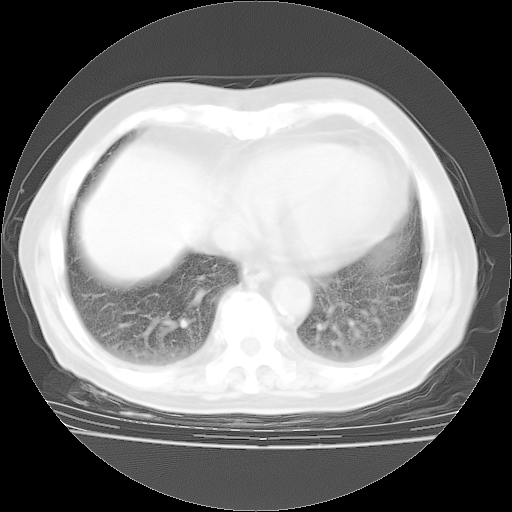

4月28日肺部CT——再次出现类似去年5月9日——透光度降低,“间质性”改变。

4月28日肺部CT——再次出现类似去年5月9日——磨玻璃样、间有“粟粒样”改变。

个人阅读4.14日肺部CT平扫:纵隔窗无异常,但肺窗示:双下肺内、后基底段有片絮状侵润影,部位以后基底段为著,以间质改变为主,呈急性肺泡炎征像,和首次住院影像学有相似之处。仅是个人读片,明日请相关专家再读片哈。其它建议同上。

1、108#的是4月14日的胸部CT(发此贴时还没看着28日的CT)。14日的胸部CT其实已经出现改变(如108#所述),个人认为28日的胸部CT除纵膈窗疑似有双侧胸膜增厚或少量胸积液(可行胸部B超明确)外,与4月14日对照病变有所加重;2、已经给予“异烟肼、利福平、乙胺丁醇”抗痨治疗?如果是,甲强龙80mg可缓慢减量;如果环磷酰胺已停用,暂不使用;3、中性粒细胞92%,明显升高,目前体温情况?注意合并细菌感染可能,使用左氧氟沙星情况下,是否联用B-内酰胺类抗菌药物?另外是查免疫全套非风湿全套。